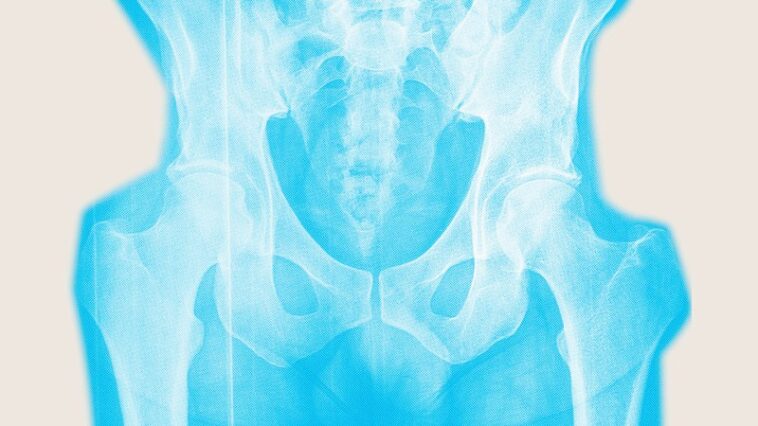

Les os affaiblis par l'ostéoporose sont plus susceptibles de se fracturer, qui peuvent être débilitants et même mortels. Les fractures de la hanche sont particulièrement dévastatrices. Environ 20% des personnes meurent dans l'année suivant une fracture de la hanche. Seulement 40 à 60% des survivants sont susceptibles de retrouver leur mobilité pré-fracture. Les limitations physiques persistantes dégradent la qualité de vie.

En janvier, le groupe de travail sur les services préventifs américains a réaffirmé sa recommandation selon laquelle les femmes de 65 ans et plus devraient être dépistées pour l'ostéoporose. Cela se fait avec un test de densité osseuse.